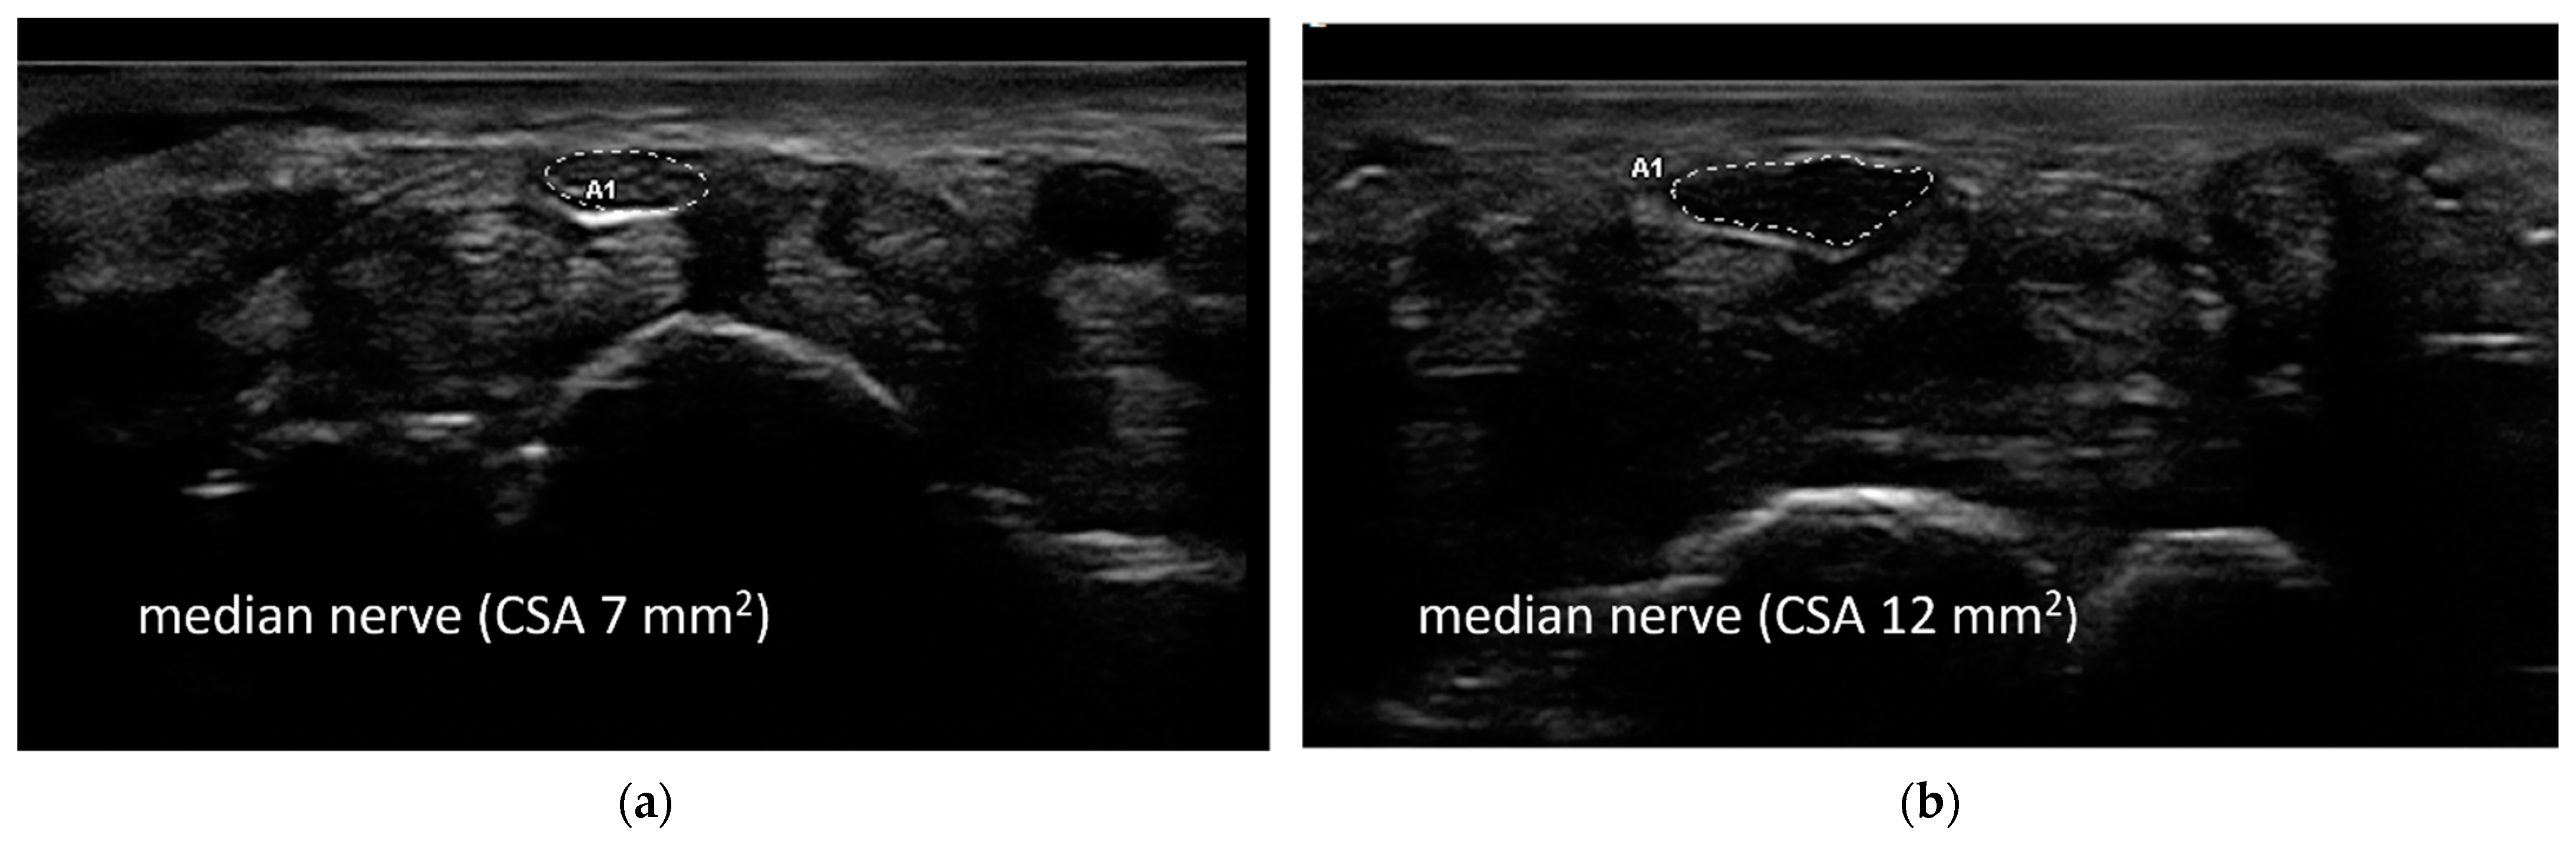

The ENoG was normal in 81% of patients, whereas the presence of CTS was detected in four patients: one right and three bilateral. The median CSA of the right median nerve at the wrist was 7 (8–7) mm2 and 6 (7–6) on the left side. The CSA was slightly increased (10–15 mm2) in one patient bilaterally, in two patients on the left side, and in one patient on the right side (Figure 1).

Axial ultrasonographic images of the median nerve at the wrist in a healthy control (a) (cross-sectional area 7 mm2) and in a patient with electrodiagnostically evaluated carpal tunnel syndrome (b) (cross-sectional area 12 mm2).